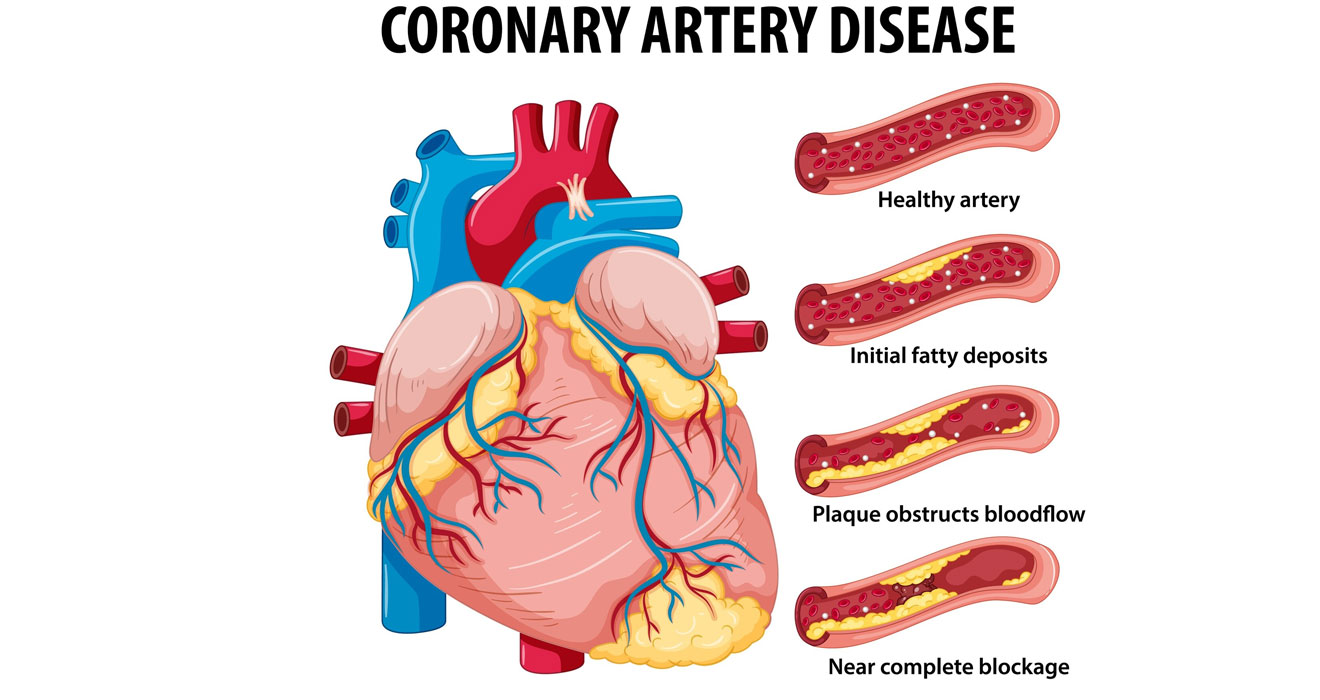

Specialized procedures to treat challenging coronary artery blockages.

Minimally invasive solutions for complex heart valve and structural issues.